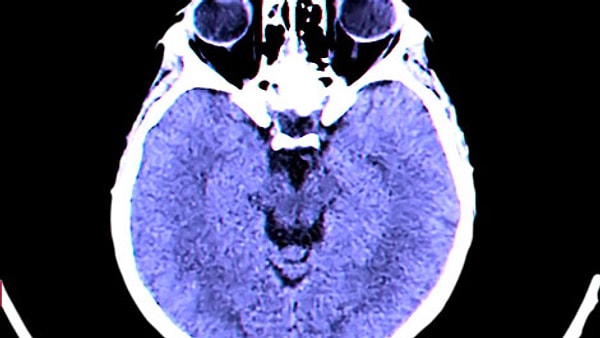

Baş araştırmacı Profesör Hadi Larijani, cihazın beyin dalgaları ve kalp işlevlerini tahlil ederek nöbetleri tespit ettiğini belirtiyor.

Araştırma grubu, binlerce saatlik beyin ve kalp kaydını yapay zeka algoritmasıyla tahlil ederek aygıtı “hayali bir kafa” üzerinde eğitti.

Sistem, nöbet öncesi ortaya çıkan elektriksel ve fizyolojik değişiklikleri tanıyabiliyor ve hastalara vaktinde ikaz vererek hazırlanma fırsatı sağlıyor. Yapay zeka, varsayımın güvenilirlik düzeyini de göstererek hastaların nöbetleri yönetmesini kolaylaştırıyor.